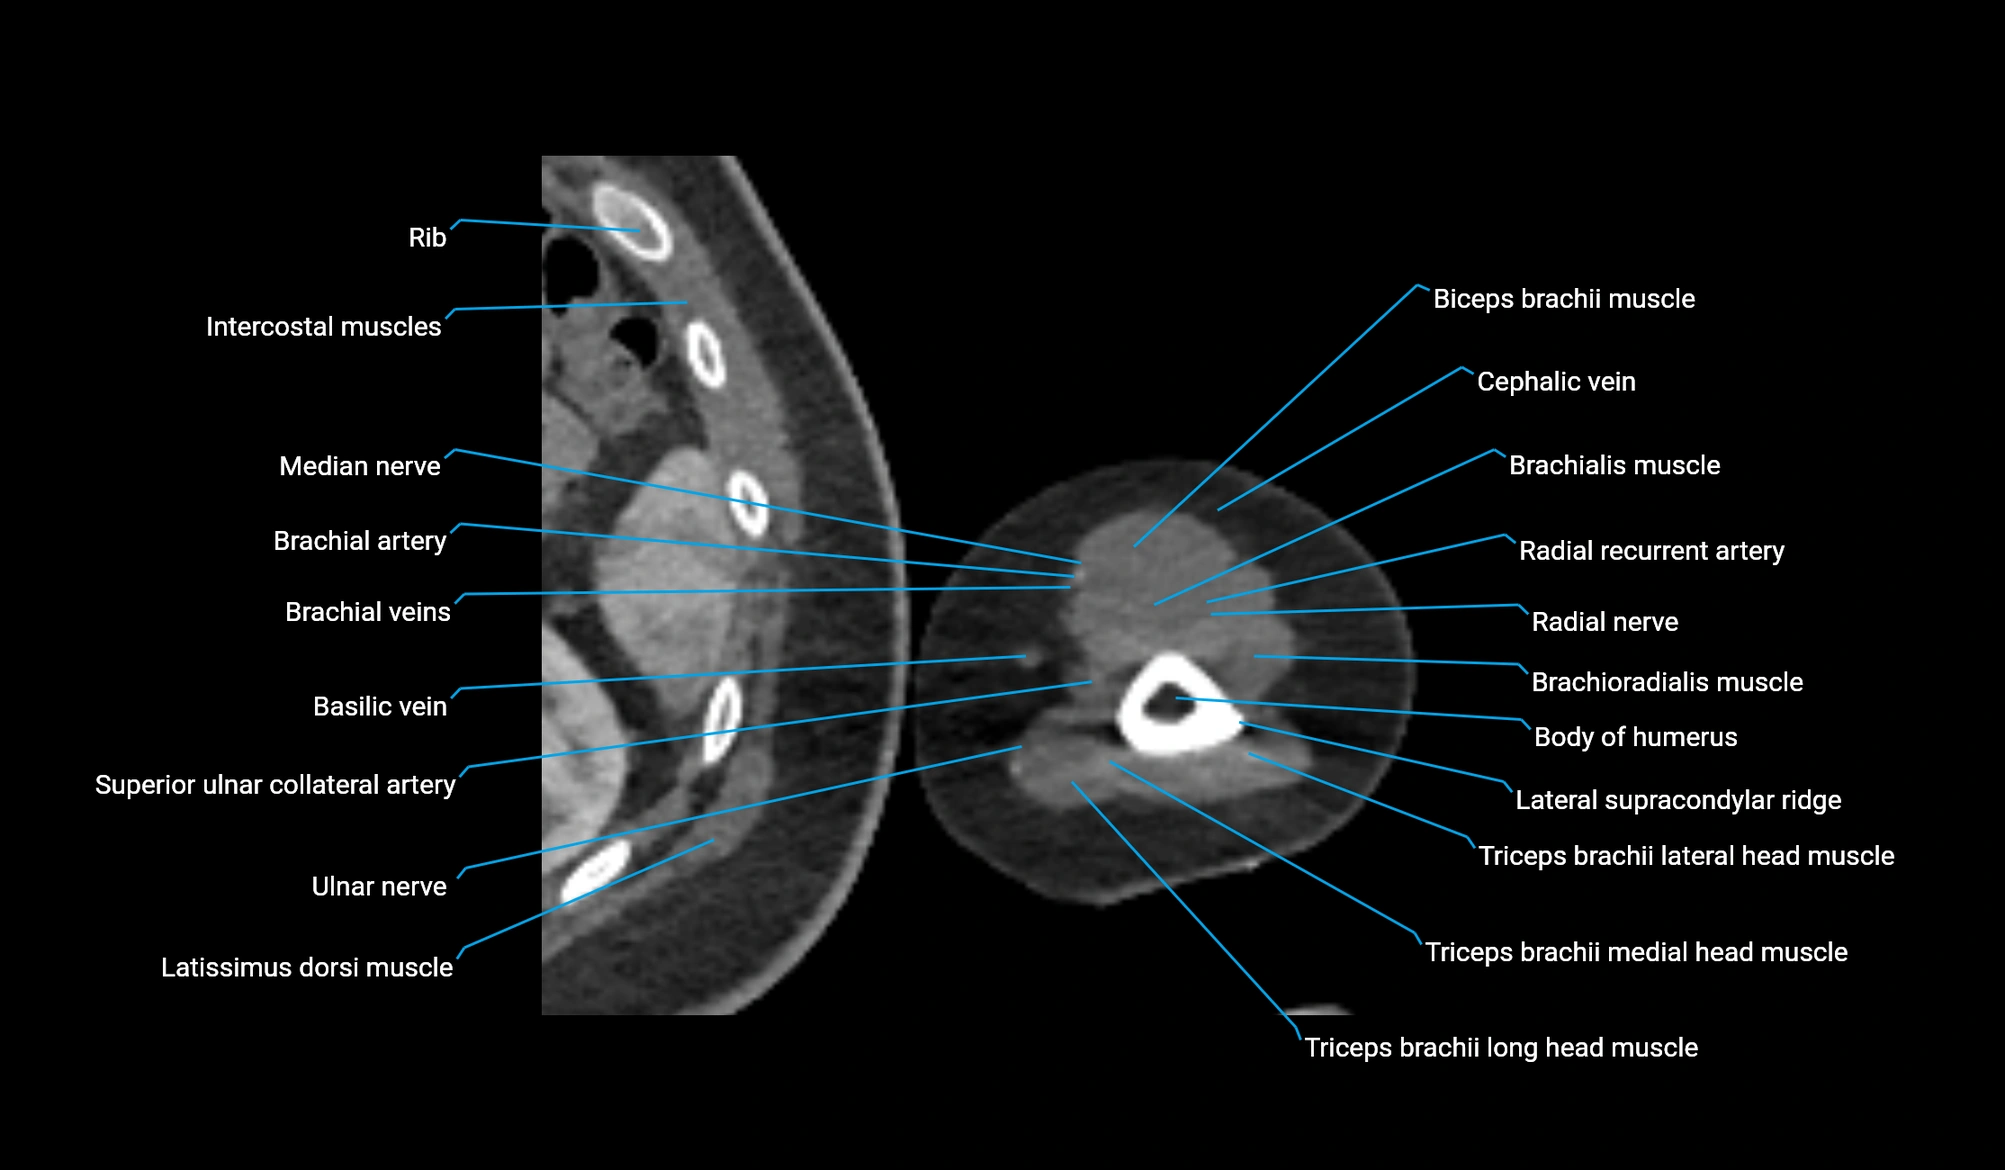

- Basilic vein

- Biceps brachii muscle

- Brachial artery

- Brachialis muscle

- Brachioradialis muscle

- Cephalic vein

- Lateral head of triceps brachii muscle

- Lateral supracondylar ridge

- Long head of triceps brachii muscle

- Medial head of triceps brachii muscle

- Median nerve

- Radial nerve

- Radial recurrent artery

- Superior ulnar collateral artery

- Ulnar nerve